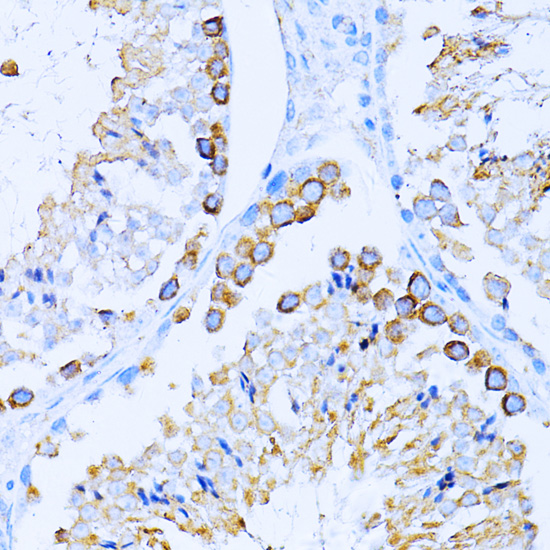

Immunohistochemistry of paraffin-embedded rat brain using CD63 antibody.

Immunohistochemistry of paraffin-embedded mouse testis using CD63 antibody. |